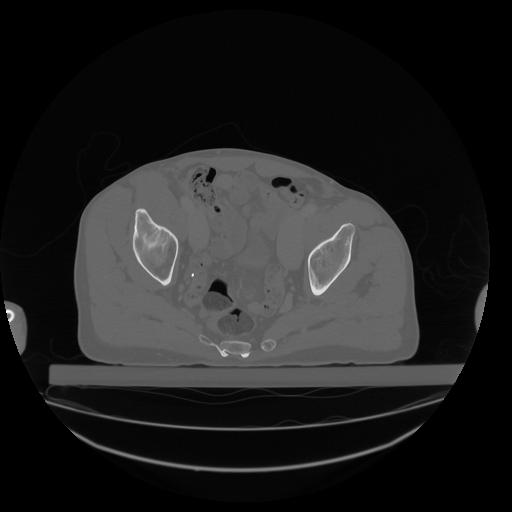

34 CUERPO,CE,Vol,1.0,CUERPO,,